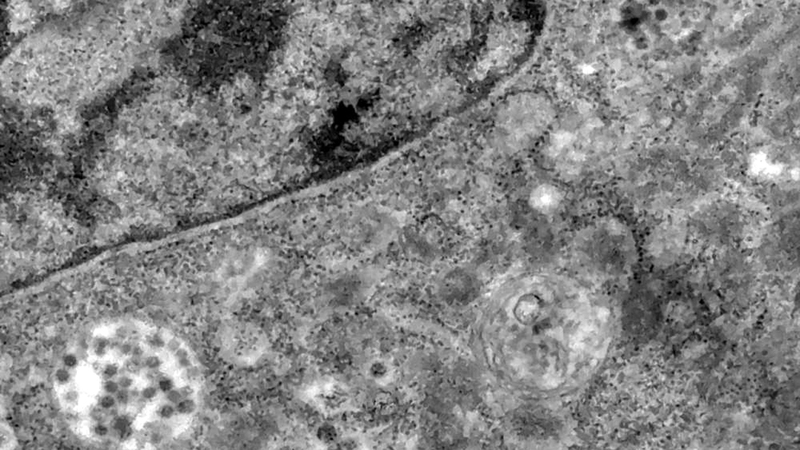

والتقط الباحثون بوساطة مجهر إلكتروني أول صورة للفيروس أثناء مهاجمته الخلايا في البرازيل، فقد صورت فرق في أنحاء مختلفة الفيروس من قبل، وتتبع الصور الفيروس بدءاً من ارتباطه بالمستقبلات على غشاء الخلية، وحتى العدوى وتكاثره داخل الخلايا، ثم الخروج وإعادة الكرّة في خلية أخرى.